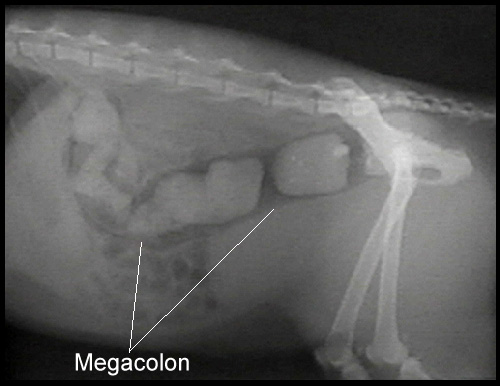

Vet: … ya… cats arent’ supposed to “poo like a human”, she has a defect called Megacolon which she’s probably had all her life.

Vet: Here’s an x-ray of your cat, do you see that mass that goes the entire length of her body? That’s feces.

Vet: Ya poo. And it’s that color because it’s a solid mass making it impossible for her to pass on her own.